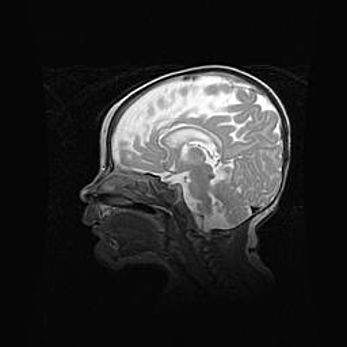

Неполная лизэнцефалия (пахигирия). Открытая гидроцефалия.

Возраст: 17 дней

Вес: 3110 г

Пол: мужской

Окружность головы: 33,5 см

Срок гестации: 35-36 недель

Лизэнцефалия—недоразвитие корковой пластинки и мозговых извилин в результате нарушения миграции нейронов коры. Поверхность мозговых полушарий гладкая. Микроскопически выявляется отсутствие нормальных слоев коры и скопление групп нейронов в подкорковом белом веществе.

Пахигирия—уменьшение числа вторичных извилин. В пораженном полушарии нервные клетки образуют толстый недифференцированный слой с неправильно расположенными нервными волокнами и группами гетеротопных клеток. Нервные клетки незрелые. Белое вещество истончено. При этом нередко аномально развит корково-спинномозговой путь.